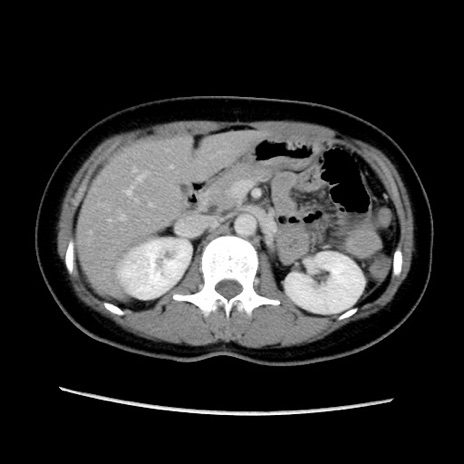

症例39(横断像)

【症例】40歳代女性

【主訴】上下腹部痛

【現病歴】2日目から下腹部痛あり。夜間は痛みで眠れなかった。昨日より上腹部痛と下痢が出現。臥位で痛みは軽快したため、休んでいた。本日になって臥位でも立位でも痛みが強くなってきたため救急要請。

【既往歴】子宮内膜症

【身体所見】部:平坦・軟、左上下腹部に圧痛あり、反跳痛あり。

【データ】WBC 21800、CRP 26.78